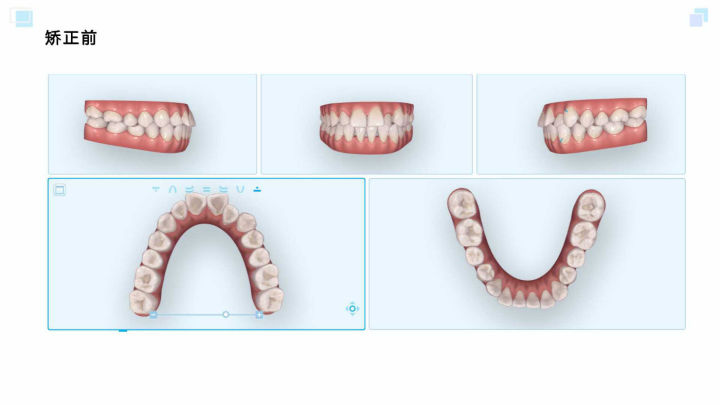

iTero口扫照

患者主诉:牙齿不齐

口内检查:

- 上颌中线正中,下颌中线右偏1mm,前牙部分反合,笑线不调。

- 磨牙关系右侧I类,左侧I类,上颌牙弓I度拥挤,上颌牙弓中段狭窄。

- 18、38垂直阻生,28未萌出。

面部检查:

- 五官基本对称,面部左右基本对称。

- 口裂大小与双侧瞳孔内缘切线宽度一致。

- 面下1/3过短,直面型。

诊断:

- 牙型:AngleI类

- 骨型:I类

- 拥挤:I度

- 前牙部分反合

- 牙弓不调、笑线不调